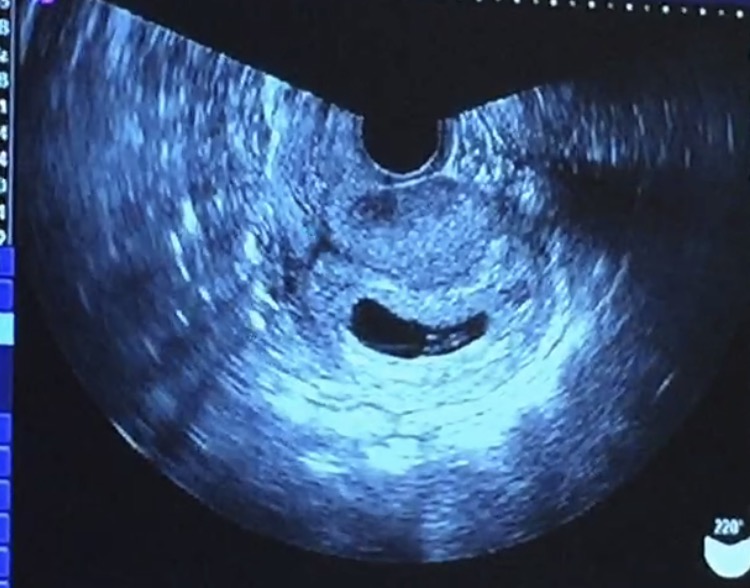

Aug 26, 18 · 妊娠9週目のエコー写真(胎児の大きさや状態) 7週目にクリニック(産婦人科)に行ってるから、次が9週目やな。 妊娠9週目のお腹のエコー写真が上↑のとおりや。 赤ちゃんの大きさが248mm、約2.48センチ!Oct 21, 15 · 妊娠15週目というと、早い人だと赤ちゃんの性別がわかってもおかしくない頃。 今日はどんな顔を見せてくれるかなぁ??性別は男の子かなぁ?女の子かなぁ? と、ドキドキしながら妊婦健診に行ってきました。 妊娠15週0日目の2d&4dエコーOct 15, 16 · ダウン症はエコー写真でわかるのでしょうか。妊娠と同時にお腹の赤ちゃんが元気かどうか、なにか先天性の病気はないかと気にしている妊婦さんも多いかもしれません。ここでは、ダウン症の可能性がある場合のエコー写真の特徴や、ダウン症の検査方法についてご紹介します。